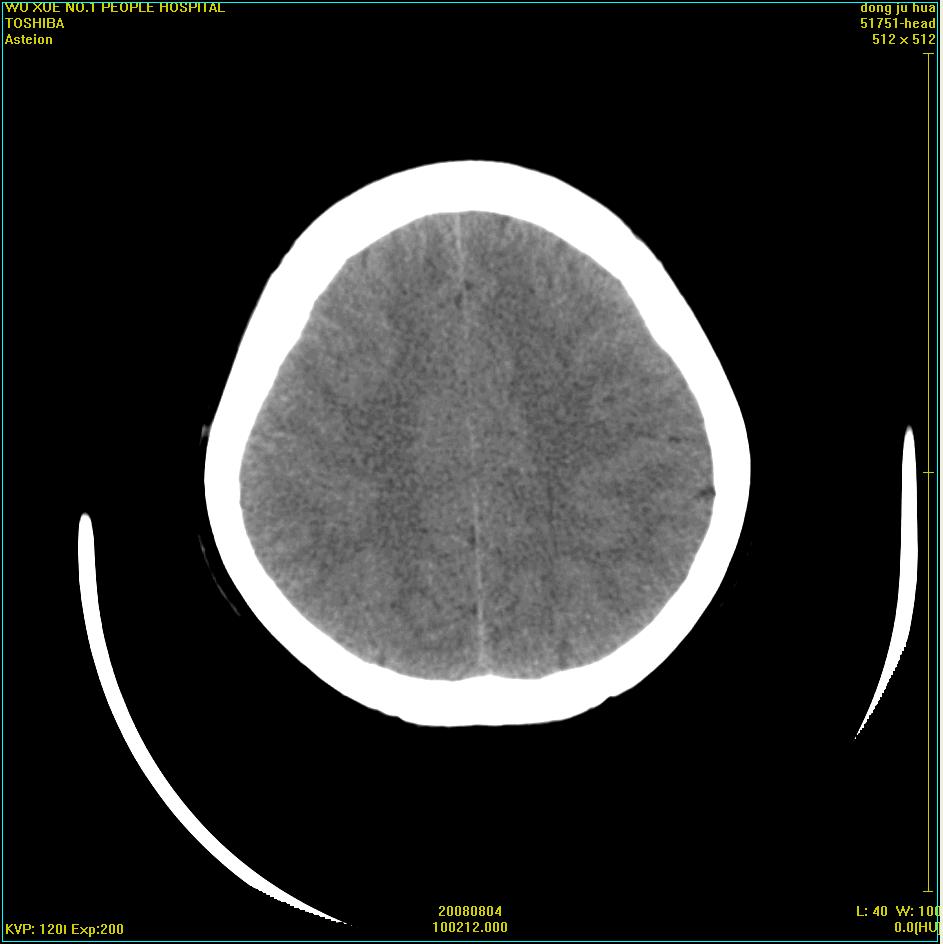

患者,女,45岁。四年前在我院做ct诊断为右侧桥小脑脚区三叉神经鞘膜瘤,已做手术。今复杳。请大家看看

三叉神经鞘膜瘤术后

看来复发了。建议mri检查。

考虑三叉神经鞘膜瘤术后复发并瘤体内出血。

三叉神经鞘膜瘤术后复发并瘤体内出血

考虑慢性扩张性血肿吧!请大家再看看,发表高见!

考虑:三叉神经鞘膜瘤术后复发并瘤体内出血。支持!

四年前做的手术,为什么大家不考虑慢性颅内血肿呢?

考虑慢性颅内血肿?症状体征有多少?能否发上?